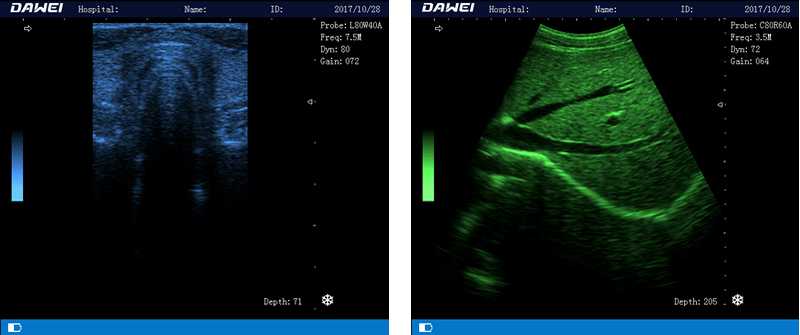

DW-580

筆記本全數字超聲診斷儀

1.優質的數字成像技術,圖像更清晰

5.體積小巧,圖像清晰,操作方便,續航能力強